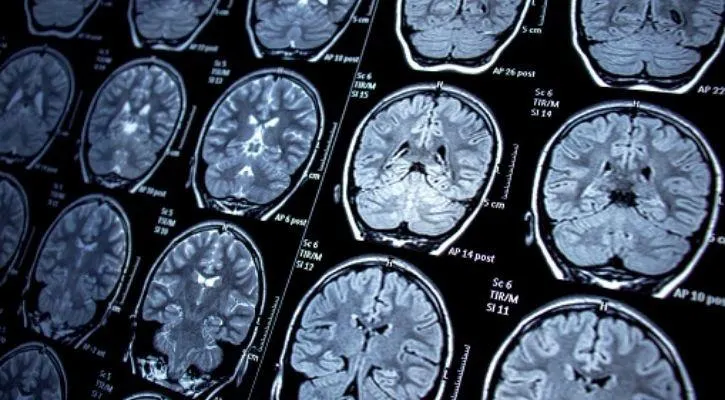

Sekelompok peneliti tidak sengaja merekam aktivitas otak seorang pasien sebelum ia meninggal. Pada hasil rekamannya terlihat bahwa otak kita seperti memutar memori masa lalu yang signifikan beberapa saat sebelum menghembuskan nafas terakhir.

Dilansir dari Live Science, rekaman memori masa lalu yang dilakukan oleh otak manusia itu diperoleh 30 detik sebelum jantung pasien berhenti berdetak. Gelombang otak yang dihasilkan mirip dengan gelombang yang biasa dilihat ketika seseorang sedang bermimpi.

Sekelompok peneliti itu menggunakan metode electroencephalogram (EEG) yang merupakan sebuah tes untuk mendeteksi aktivitas elektrik otak yang abnormal. Melalui metode tersebut, peneliti ingin melihat perkembangan pada otak pasien tersebut.

Sayangnya, pasien tersebut terkena serangan jantung mendadak dan menghembuskan nafas terakhirnya. Peristiwa ini membuat para peneliti merekam aktivitas pada orang yang sedang sekarat untuk pertama kalinya. Peneliti berhasil merekam aktivitas pria tersebut selama 900 detik.

Berdasarkan hasil rekaman tersebut, terdapat reaksi dan pergerakan yang tidak biasa pada 30 detik sebelum dan sesudah pasien tersebut meninggal.